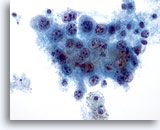

画像 3:肺FNA、肺大細胞癌 腫瘍細胞は、このシート内に見られる数個のアポトーシス細胞より大型です。細胞質の保存状態は良好であり、量が中程度で密度が高く、微細な空胞化が見られます。扁平上皮への分化の特徴である細胞間橋を思わせる細胞変化が局所的に見られます。核は円形から卵円形を呈し、結合性が疎のクロマチン集塊および肥厚化した滑面核膜が認められます。核小体は目立ち、不整形を呈し、単個から複数個見られます。高いN/C比を示します。

60倍

画像 3

肺FNA、肺大細胞癌

腫瘍細胞は、このシート内に見られる数個のアポトーシス細胞より大型です。細胞質の保存状態は良好であり、量が中程度で密度が高く、微細な空胞化が見られます。扁平上皮への分化の特徴である細胞間橋を思わせる細胞変化が局所的に見られます。核は円形から卵円形を呈し、結合性が疎のクロマチン集塊および肥厚化した滑面核膜が認められます。核小体は目立ち、不整形を呈し、単個から複数個見られます。高いN/C比を示します。

60倍